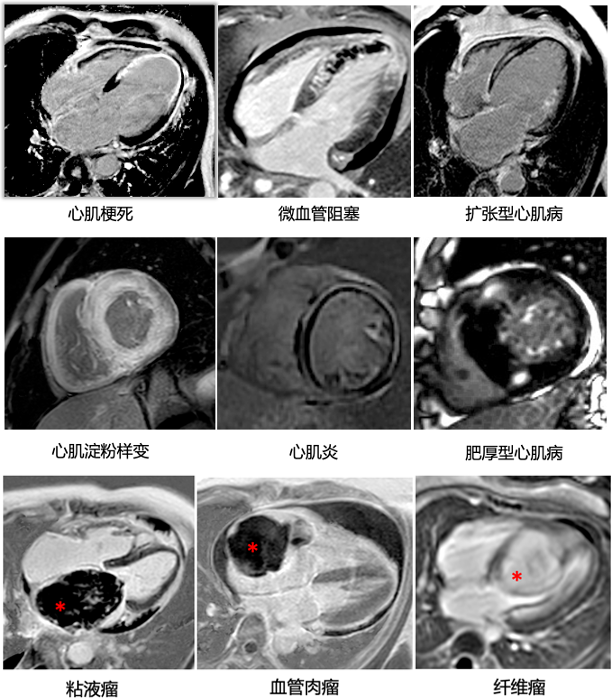

2. CMR增强检查能够在体评估心肌组织特征,实现 “病理影像化”

磁共振通过多参数成像,特别是结合钆对比剂的应用,能够显示心血管疾病的组织学特征,具有其他任何影像学方法不可比拟的独特优势。心血管的组织学改变,包括炎症(充血和水肿)、坏死和纤维化等(图2),甚至对于心脏占位的定性评估,过去只能通过心肌穿刺活检或尸检方能获得,而磁共振多模态组织学成像可将其精准识别和鉴别。换言之,磁共振成像实现了在体组织“病理影像化”,不仅有助于精准诊断,而且还能够对患者行预后判断和风险评估,以便进行针对性的预防与治疗。

2. 不同心脏疾患的钆对比剂延迟增强(LGE)表现